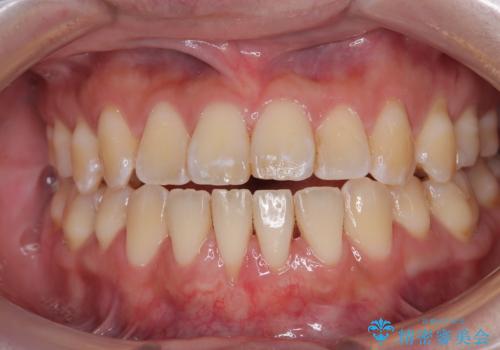

矯正の後戻りによるすきっ歯と歯肉退縮 根面被覆と部分矯正

- 学生時代の矯正治療の後戻りと、それに伴う下顎前歯西肉退縮を気にして来院された患者様です。

舌の突出癖が著しく、それが原因で後戻りと歯肉退縮を起こしている状態でした。

舌のトレーニングをしっかりと行っていくことを前提に、歯肉移植による根面被覆と、部分矯正によるすきっ歯の改善を行うこととしました。

歯肉移植と矯正治療後には非常に満足のいく仕上がりとなりましたが、舌の突出癖は残存しており、今後歯肉退縮とすきっ歯になるリスクを抱えた状態での治療終了となりました。